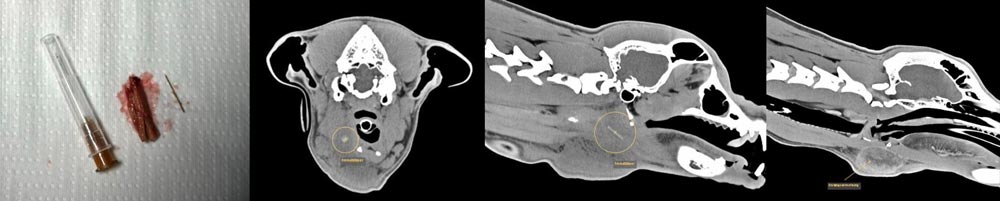

Dank des CTs können wir detaillierte 3D-Bilder von Organen und Geweben erstellen und so Erkrankungen erkennen, die mit herkömmlichen Methoden schwer sichtbar wären. Dies ist besonders hilfreich bei der Diagnose von Tumoren, Verletzungen oder Erkrankungen der inneren Organe und des Nervensystems.